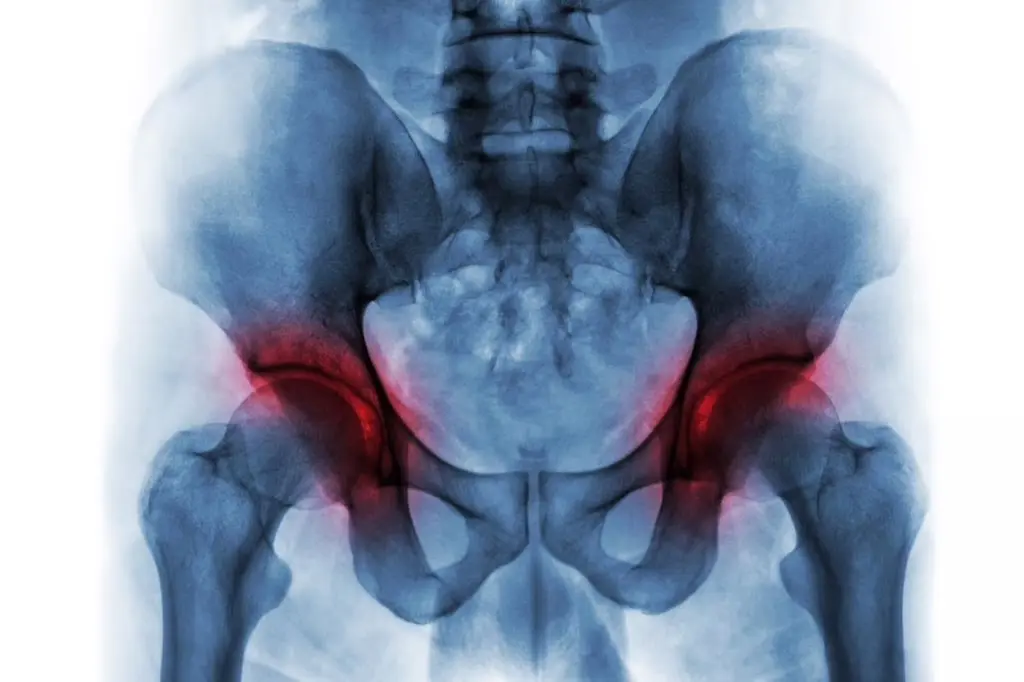

به گزارش انتخاب و به نقل از هلث دی؛ این جراحی معمولاً برای افرادی که دچار آسیب شدید غضروف در مفصل ران هستند انجام میشود. آسیب به این مفصل میتواند منجر به درد در کشاله ران، باسن و یا پهلوی ران شود. در برخی موارد، درد ممکن است به زانو هم انتشار پیدا کند.

• آرتروز (فرسایش غضروف مفصل)

• آرتریت التهابی (مانند آرتریت روماتوئید یا آرتریت پسوریاتیک)

• نکروز استخوانی (از بین رفتن خونرسانی به استخوان که منجر به آسیب غضروف میشود)

• آرتریت ناشی از ضربه (آسیب به مفصل پس از شکستگی قبلی)